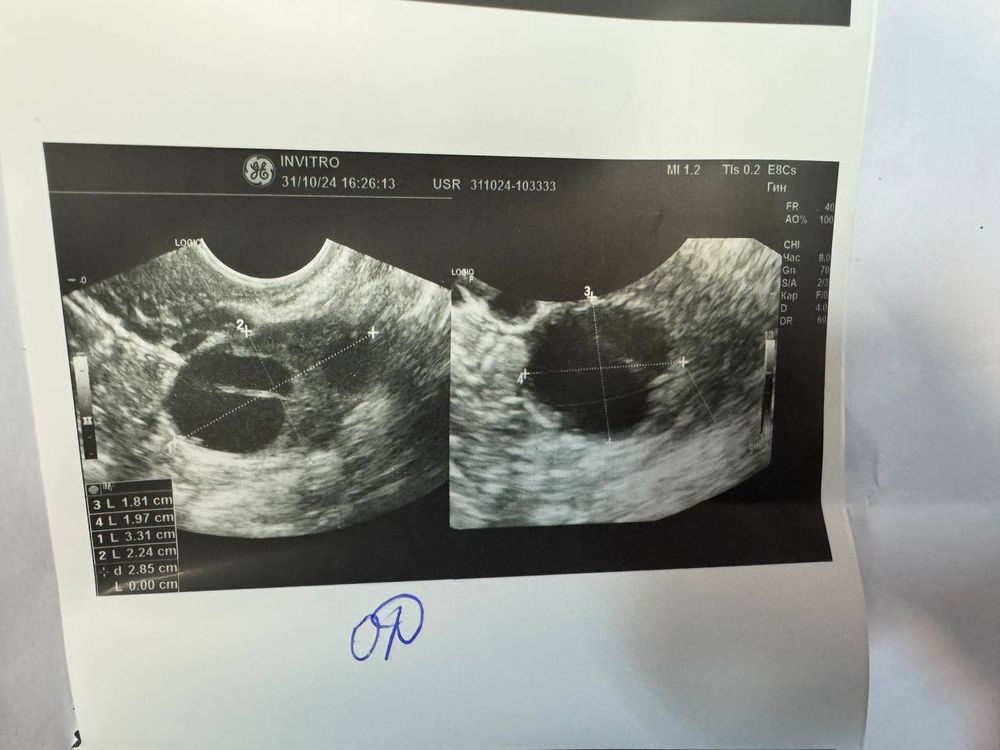

Девочки,помогите пожалуйста. Я третий цикл принимаю инозитол, на двух циклах овуляция была на 18ДЦ, в этот раз пошла на УЗИ на 17ДЦ и врач сказала ,что видит хорошее ЖТ и что овуляция уже была,конечно примерно когда она была не может сказать. У меня сейчас идет 34 ДЦ, грудь ужасно болит, всю неделю подтягивал низ живота как будто сейчас польет и белые выделения. Но,месячных нет( сделала тест вечером он показал одну полоску( конечно наверное лучше делать тесты утром). Не могу понять, что со мной. Может у кого так было ?